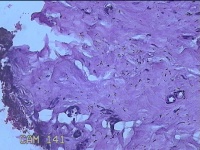

性别

女

年龄

27岁

临床诊断

乳腺脓肿

一般病史

发现右侧乳腺脓肿1个月余,伴局部疼痛不适。

标本名称

右侧乳头下方结节

大体所见

灰白暗红色结节0.8x0.5x0.3cm一个,表面糜烂。

组织没固定好